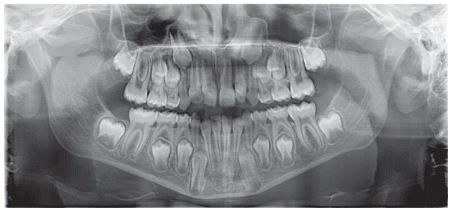

Case 2

The patient was a growing female child who presented during early mixed dentition with an anterior crossbite associated with a deep overbite and a marked sagittal discrepancy (Figures 12–19). The initial clinical examination revealed a negative overjet, complete anterior deep bite, and a functional Class III occlusal pattern. Extraoral assessment showed a flattened facial profile, while cephalometric analysis confirmed a skeletal imbalance characterized by increased SNA and SNB values, an ANB of 0°, negative Withs appraisal, and significant dentoalveolar compensations, including proclination of both upper and lower incisors (Table 3). The vertical pattern was predominantly hypodivergent, suggesting a high risk of unfavorable mandibular growth progression if left untreated. Given the patient’s young age and growth potential, an early interceptive treatment was planned to use the AMCOP® TC appliance, with the aim of correcting the anterior crossbite, improving neuromuscular balance, and guiding sagittal and vertical development during growth. The appliance was worn nightly and for additional daytime hours, according to patient compliance.

After 18 months of treatment, a clear clinical improvement was observed. Intraoral examination demonstrated complete correction of the anterior crossbite, with establishment of a positive overjet and normalization of the anterior occlusal relationship. The deep bite was reduced, allowing more functional anterior guidance. Occlusal relationships improved toward a stable dental Class I, and the need for excessive dentoalveolar compensation was reduced. Cephalometric reassessment showed an overall improvement in sagittal relationships and incisor inclinations, with a trend toward normalization of the previously altered parameters. These findings indicate that early functional therapy with the AMCOP® TC appliance was effective in intercepting the developing Class III malocclusion, improving occlusal function, and potentially reducing the severity of future skeletal discrepancies (Table 4).